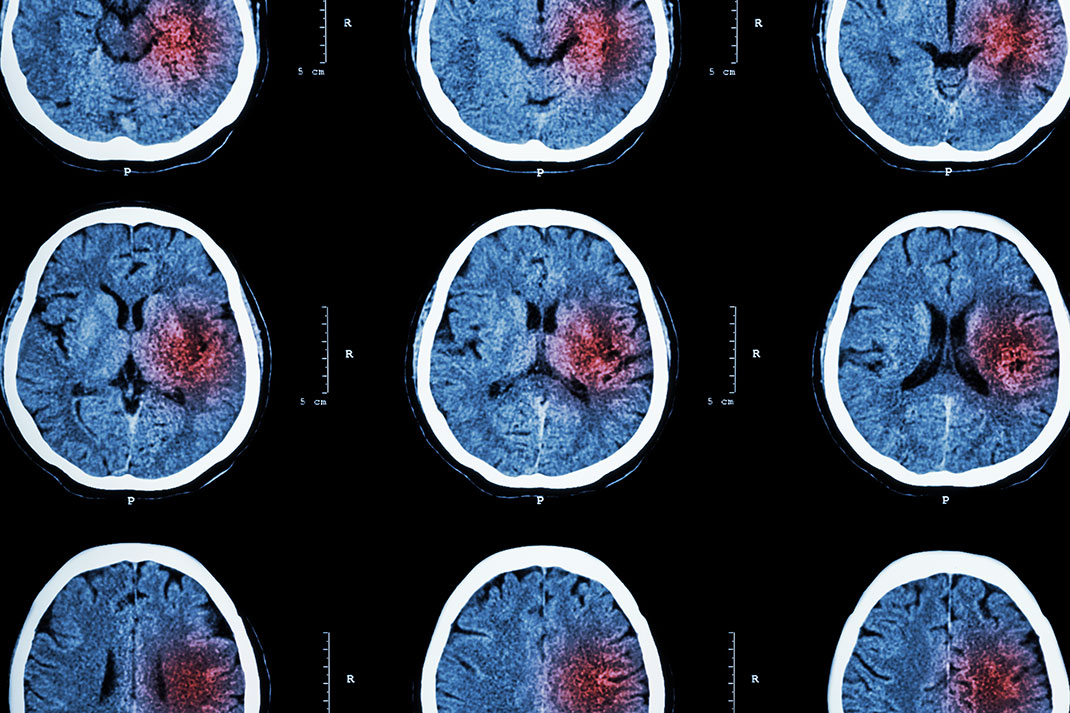

En injectant des cellules souches dans le cerveau de patients souffrant de séquelles suite à un accident vasculaire cérébral, une équipe de scientifiques américains a obtenu des résultats encourageants. Suite à cette transplantation, les sujets ont ainsi obtenu une nette amélioration de leur état sans aucune complication, un véritable pas de géant dans le domaine médical. Nous devons les résultats enthousiasmants de ce traitement à l’équipe de Gary Steinberg, de l’université Stanford en Californie.

Un accident vasculaire cérébral (AVC) est un déficit neurologique soudain d’origine vasculaire causé par une hémorragie ou par un vaisseau sanguin bouché, entraînant l’interruption de la circulation du sang vers le cerveau. En France, ils frappent près de 150 000 personnes par an. Les AVC sont la première cause de handicap dans le monde entier. De nombreux centres de recherche tentent de trouver un moyen de soigner les patients atteints de séquelles, notamment à l’aide de cellules souches mésenchymateuses extraites de la moelle osseuse et du tissu adipeux de donneurs.

Pour tester les cellules souches, le scientifique Gary Steinberg et son équipe de chercheurs ont ainsi sélectionné dix-huit patients. Tous ont été victimes d’un accident neurologique entre six mois et trois ans plus tôt et leurs séquelles sont principalement motrices. Ainsi certains d’entre eux ne pouvaient plus marcher du tout.

L’équipe de chercheurs a donc injecté des cellules mésenchymateuses modifiées génétiquement directement dans la zone touchée du cerveau des patients. Aucun problème de tolérance notable n’a été relevé suite à cela, bien au contraire les scientifiques sont parvenus à une conclusion très encourageante : ils ont observé une certaine amélioration de l’état des patients suite à l’injection. « Ce n’était pas simplement qu’ils ne pouvaient pas bouger leur pouce et qu’ils en deviennent capables. Des patients qui étaient en fauteuil roulant remarchent », s’extasie Gary Steinberg.

Mais les chercheurs se sont rendu compte que ce progrès soudain n’est pas uniquement dû à l’injection des cellules souches car celles-ci ont totalement disparu au bout d’un mois. Ils sont donc parvenus à la conclusion que les cellules transplantées agissent en aidant le cerveau à se réparer puis à cicatriser grâce à la sécrétion de plusieurs substances. Jusqu’à cette découverte encourageante, les médecins n’avaient pas de véritable solution à proposer à leurs patients car six mois après un AVC les lésions neurologiques sont difficiles à renverser. Ainsi cette méthode donne un véritable espoir à toutes les personnes atteintes de séquelles.

Tout de même il est important de noter que les chercheurs doivent continuer à tester sur d’autres patients ce traitement afin de comparer l’évolution des cellules souches sur différents métabolismes. L’équipe américaine menée par Gary Steinberg envisage justement de faire d’autres essais sur 156 autres patients. Les chercheurs veulent ainsi tester l’injection sur une partie de ces sujets et faire « une fausse intervention chirurgicale » sur l’autre partie des patients afin de comparer l’influence du traitement sur leur état et comprendre l’évolution des cellules injectées dans leur cerveau.